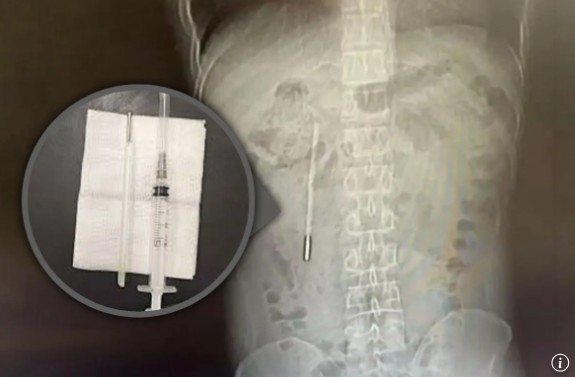

14일(현지시각) 외신 매체 홍콩 사우스차이나모닝포스트(SCMP)에 따르면, 중국 남동부 저장성 원저우 출신 왕씨(32)는 복통을 호소하며 병원을 찾았다. 검사 결과, 십이지장에 이물질이 발견됐으며 의료진은 수은 온도계를 의심했다. 온도계 끝부분이 장벽을 압박하고 있어 장 천공과 내부 출혈 위험이 큰 상태였다.

왕씨는 과거 12살에 온도계를 실수로 삼켰지만, 부모에게 혼날까 두려워 이를 숨기고 살아왔다고 밝혔다. 제거 수술은 20분 만에 끝났고, 온도계 형태는 그대로였지만 온도를 표시하는 눈금은 사라진 상태였다.